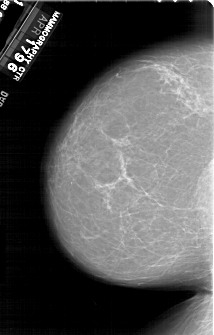

A_1923_1.LEFT_MLO

LEFT_MLO LINES 6871 PIXELS_PER_LINE 4216 BITS_PER_PIXEL 12 RESOLUTION 43.5 NON_OVERLAY